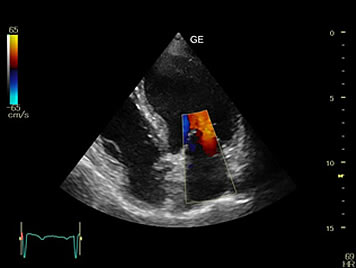

Vascular Doppler Scan

Your doctor may suggest a Doppler ultrasound exam if you show signs of decreased blood flow in the arteries or veins of your neck, arms or legs.

A reduced amount of blood flow may be due to a blockage in the artery, a blood clot inside a blood vessel, or an injury to a blood vessel. This can help to screen people who are at risk of strokes, heart attacks and pulmonary embolism(blood clot travelling to the lungs).